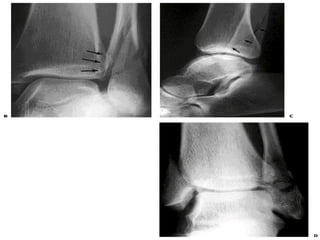

X - RAYS

   On plain x-rays – there is continous

condensed sub chondral bone around

the talus that extends from sub

chondral bone of distal tibia to medial

aspect of fibula

   AP and LATERAL

   MORTISE VIEW

   STRESS or OBLIQUE VIEW (cobb’s)

A-P VIEW

   Tibio-fibular overlap

   <10mm implies

syndesmotic injury

   Tibio-fibular clear

space

   >5mm implies

   Talar tilt

   >2mm is considered

abnormal

MORTISE VIEW

AP view of ankle with

foot internally

rotated

Abnormal findings:

   medial joint space

widening

   tibia/fibula overlap

<1mm

LATERAL

VIEW

   Posterior malleolus

fracture

   Subluxation of the talus

   Angulation of distal fibula

   Talus fractures

   Calcaneus fractures

STRESS VIEWS

   Demonstrate ligamentous or syndesmotic

disruption

   May require sedation or hematoma block

   Comparison with contralateral ankle